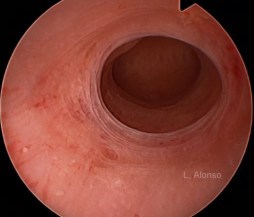

El diagnóstico suele hacerse mediante la ecografía, estos úteros habitualmente no tienen un buen desarrollo a nivel endometrial, permaneciendo generalmente con poco desarrollo o engrosamiento del mismo. La medida del volumen endometrial puede ser útil en el diagnostico de esta patología, estableciéndose el limite en menos de 6-7 mm en el día 10-14 del ciclo. La utilización de la ecografía tridimensional también puede ayudar en el diagnóstico. La prueba que más nos ayuda es la histeroscopia en la que se aprecia una cavidad tubular, sin espacio suficiente, en la que no se identifica una anatomía uterina normal.

El tratamiento en estos casos es la realización de una metroplastia lateral histeroscópica utilizando generalmente el asa de Collins. Este asa se utiliza para incidir y cortar las paredes laterales uterinas que causan el estrechamiento de la cavidad uterina. Es un procedimiento que se realiza enteramente bajo visión endoscópica, siendo seguro y eficaz.